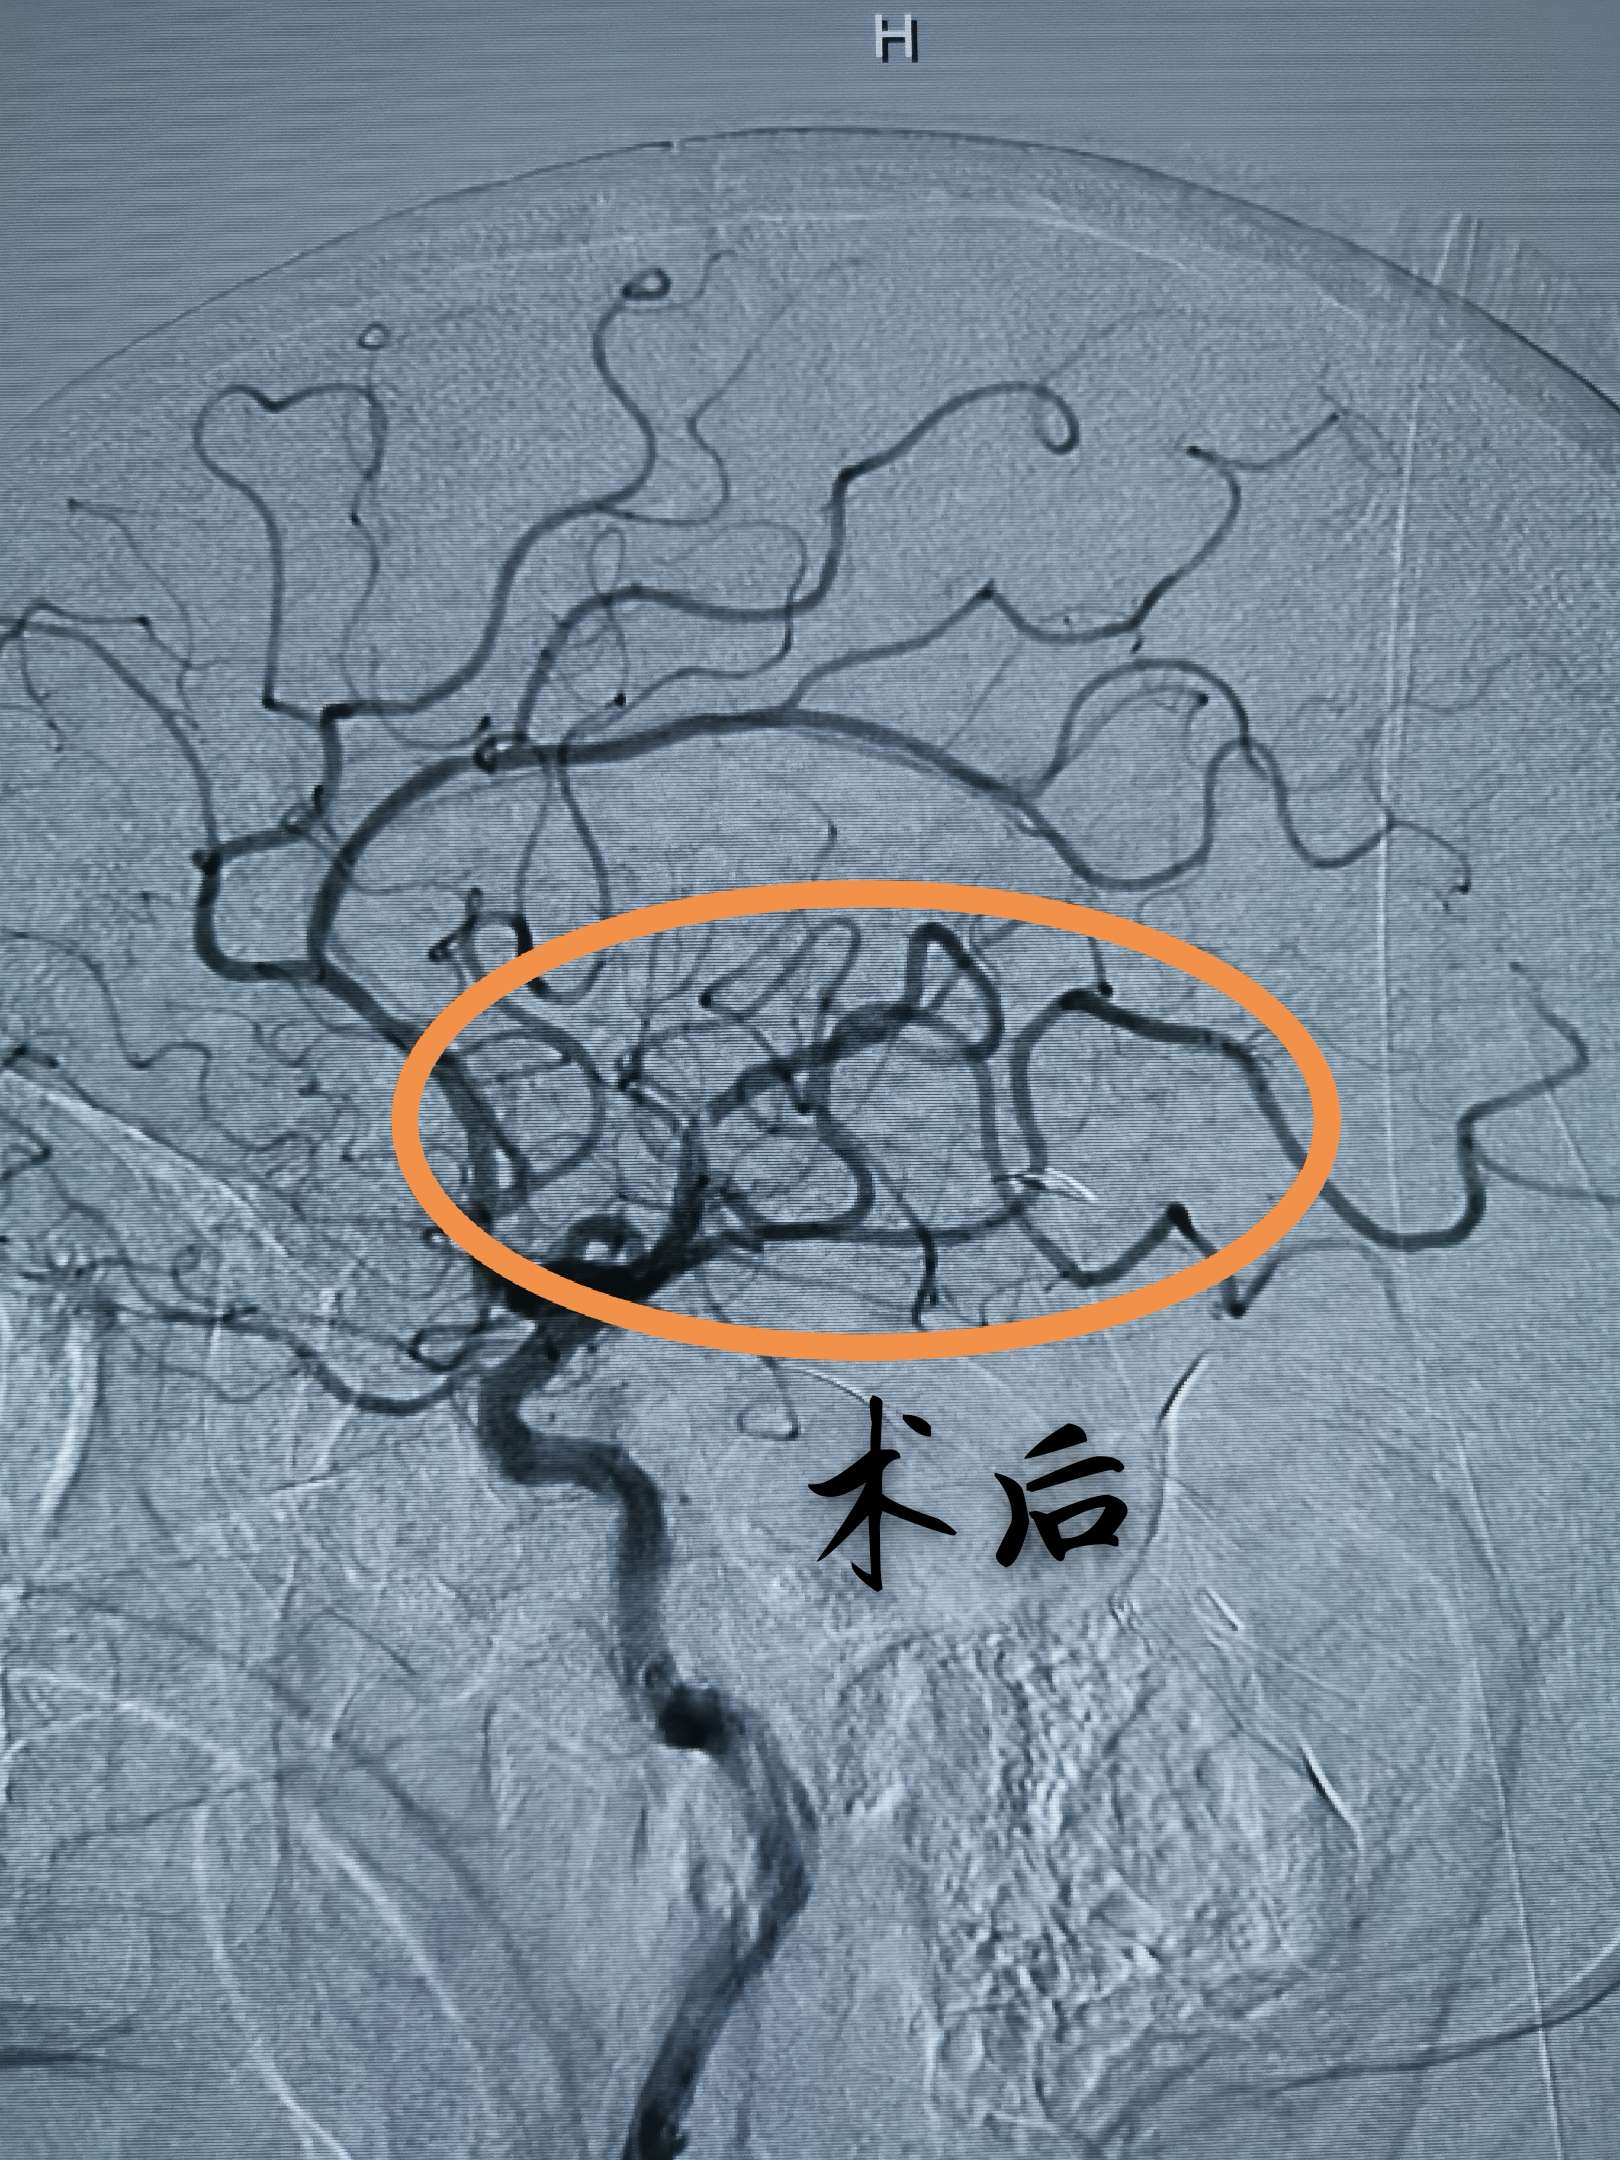

正侧位造影,血栓大部分被清理,有少量残留,但远端血流通畅,此时,患者开始说话,言语清晰流利,左侧肢体肌力开始恢复,静脉泵入替罗非班,收台

术后即刻,左侧肢体肌力明显恢复,已经能够抬离床面,此时,距离发病5小时,闭塞动脉完全开通